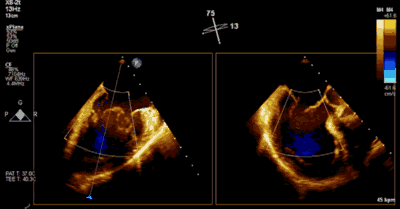

▲ 术前超声检查显示重度二尖瓣反流

▲ 术后超声检查显示轻度二尖瓣反流

患者为73岁老年男性,既往合并冠心病、持续性心房颤动、肾功能不全病史,此次主诉“反复胸闷气促3月余”入院。诊断:心脏瓣膜病 二尖瓣脱垂伴重度关闭不全 心功能Ⅲ级(NYHA分级)。术前经胸超声心动图示:左房扩大,二尖瓣前后叶冗长、P2脱垂合并重度反流(Type II类 DMR/MR4+)。心脏测值:LA 54 x 58mm,LVD 60mm,EF% 60%,PASP 36mmHg。经食管超声心动图示:二尖瓣环左右径38mm,反流束缩流颈宽度为8.5mm,EROA 0.72cm2(PISA),舒张期二尖瓣口平均跨瓣压差2mmHg。

王焱、王斌教授团队通过术前和台北荣民总医院(Taipei Veterans General Hospital)宋思贤教授进行了详细的讨论并制定了最优的手术策略,同时术中视频连线获得宋思贤教授的技术支持,爱情岛论坛 超声内科苏茂龙教授负责术中超声心动图引导。患者全麻以后,在经食道超声心动图和X射线引导下,经股静脉入路,将MitraClip瓣膜夹顺利送至二尖瓣前后叶交界中心处,成功捕捉二尖瓣前叶A2和后叶P2,经超声心动图反复确认瓣叶夹持牢固后,测定有效夹持长度11mm,评估反流量降至微量,释放瓣膜夹,超声心动图评估瓣膜夹位置和功能良好,测定左房压降至11/6mmHg,再次评估反流量仍为微量,手术顺利完成。